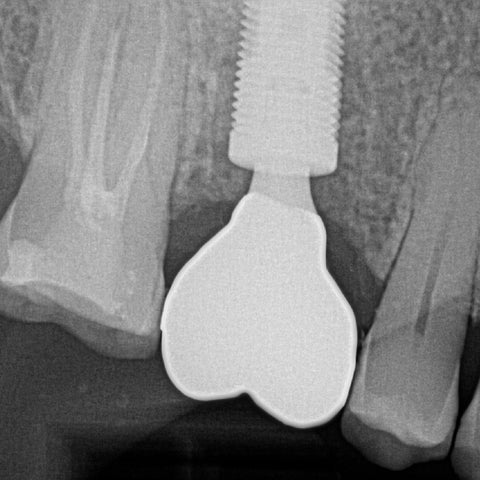

Proper Seating of an Implant One Abutment